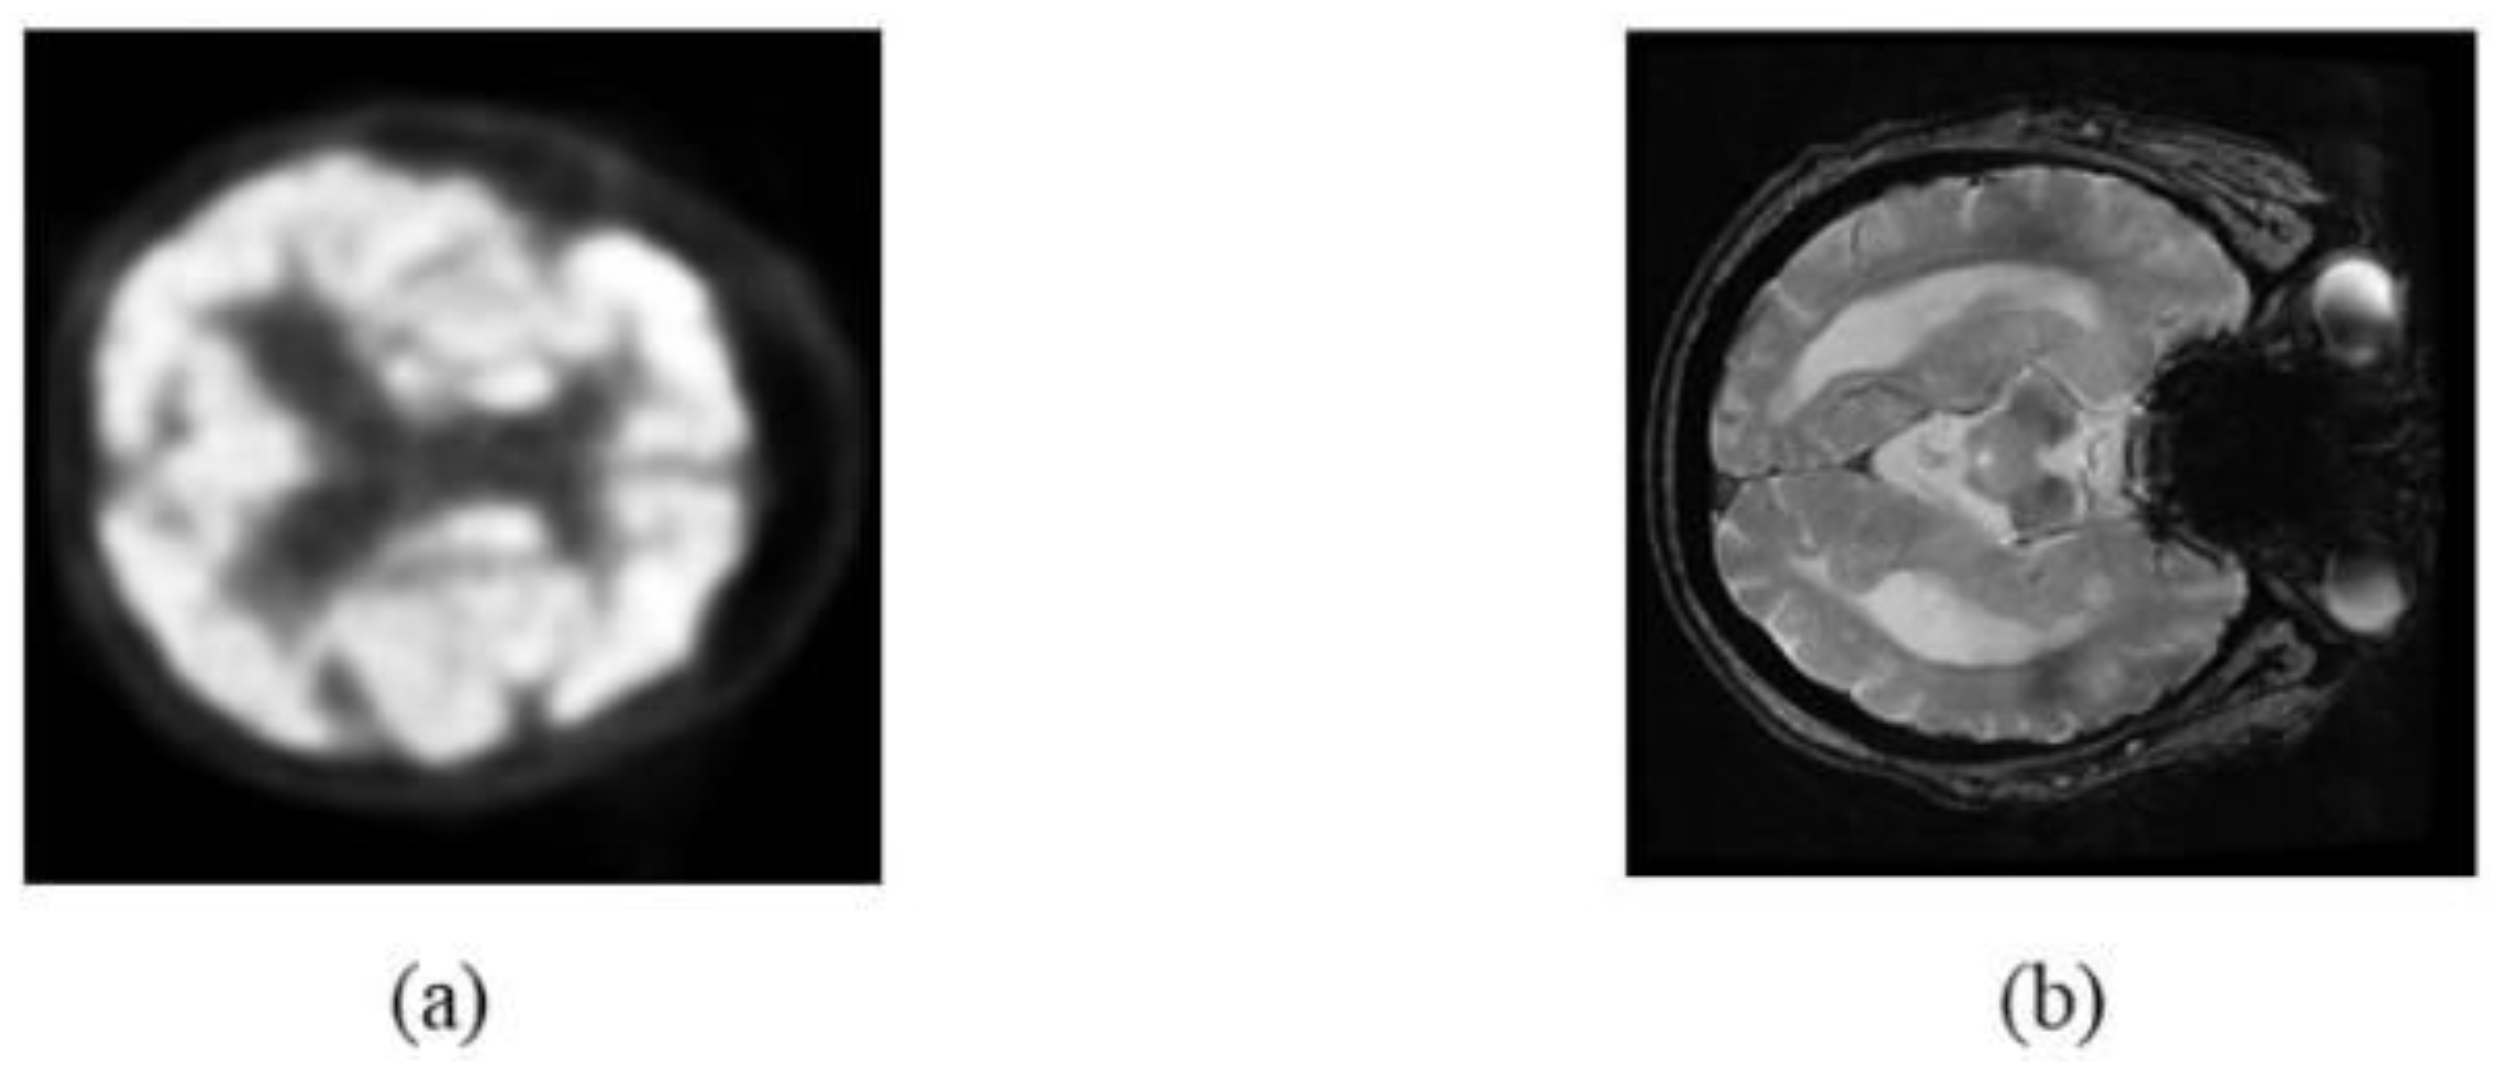

2.1. Image Data

2.2. Image Preprocessing

2.3. Image Registration